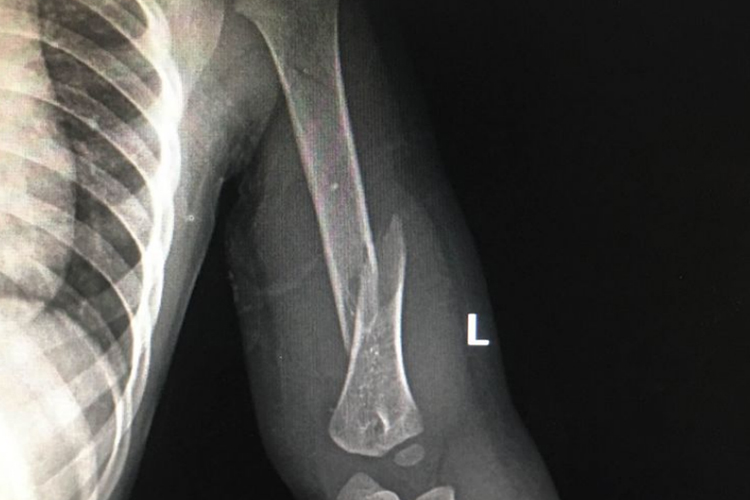

骨折重叠移位为完全骨折表现,多发生于长骨处,断裂处骨骺和干骺端远折端向近侧位移,形成刺刀样重叠畸形。患者还可有明显疼痛症状,移动时加重。骨折端肿胀、畸形,出现移位可导致肢体短缩、弯曲,并伴有活动功能的丧失。

骨折重叠移位时,骨折端活动可引起疼痛,损害周围软组织,增加出血,甚至可引起休克。因此经初步检查,对骨折处肢体予以固定处理。固定时应防止皮肤受压损伤,四肢固定要露出指、趾尖,便于观察血液循环,经处理后需及时就医,进行手术复位固定处理,后期应尽早在专业人士指导下进行康复训练,以促进恢复。